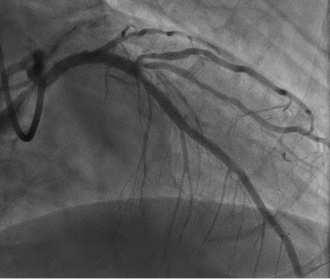

治療の一例

左前下行枝の閉塞部にステントを留置することにより、再灌流が得られた。